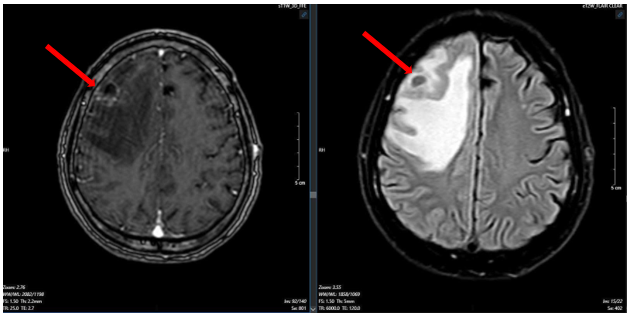

Bệnh nhân được chụp cộng hưởng từ sọ não, phát hiện khối u vùng trán phải, kích thước 17 x 20 mm gây phù não rộng xung quanh theo dõi tổn thương thứ phát

Hình 1. Hình ảnh cộng hưởng từ sọ não ngày 25 tháng 03 năm 2025 (hình bên trái: xung T1; hình bên phải: xung T2) cho thấy khối u não vùng trán phải (mũi tên).